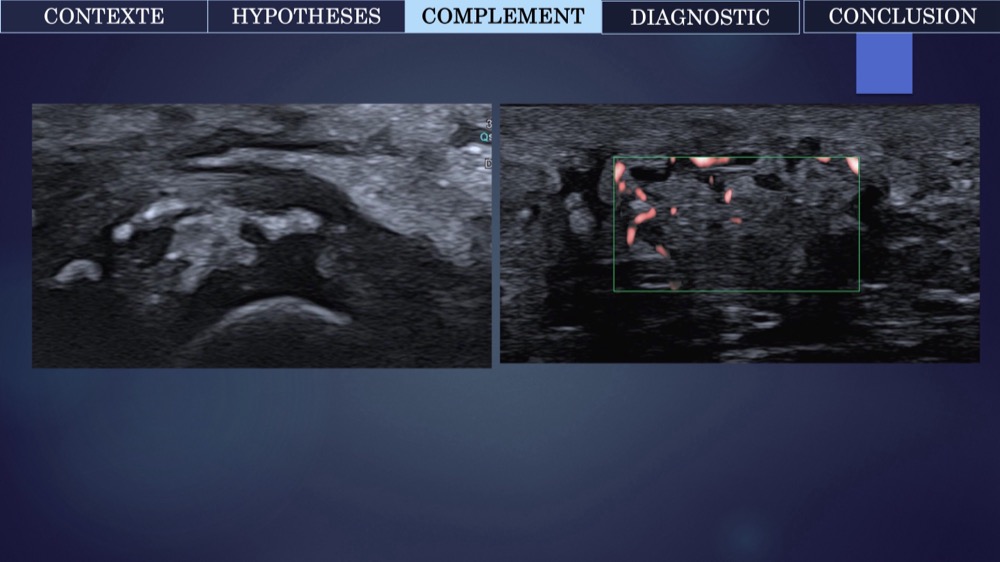

Aliénor Campredon 18/05/2022